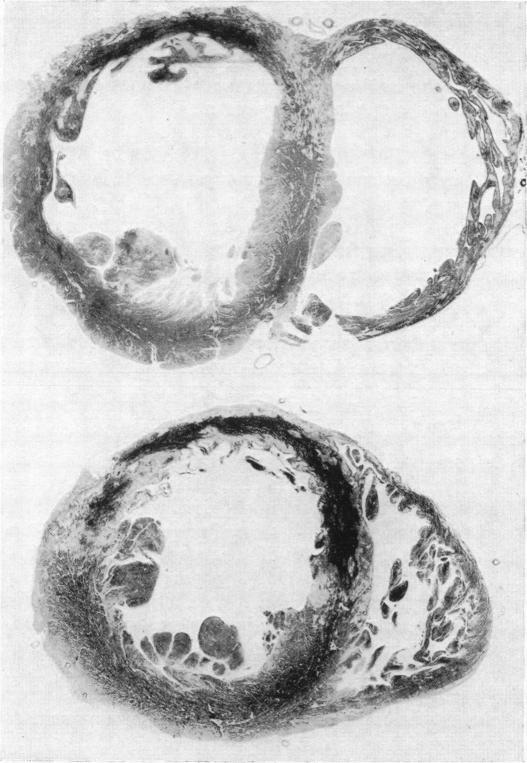

Total and peripheral blood flow in acute myocardial infarction.

Br Heart J. 1957 Jan;19(1):117-28. doi: 10.1136/hrt.19.1.117.